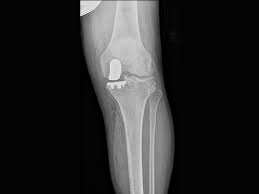

Unleash Your Mobility Potential: Advanced Arthropl...